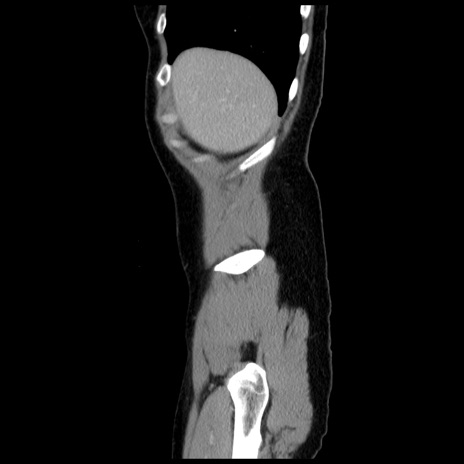

冠状断像

【症例】 50歳代女性

【主訴】 腹痛

【現病歴】前日生レバーを食べた。今朝に排便あり。 昼前に突然発症の腹痛を生じ、当院救急外来を受診した。

【既往歴】 子宮筋腫にてで子宮全摘後

【身体所見】 意識清明、腹部:平坦、軟、下腹部やや左を中心に圧痛・反跳痛あり、筋性防御あり

【データ】WBC 7800、CRP 0.07